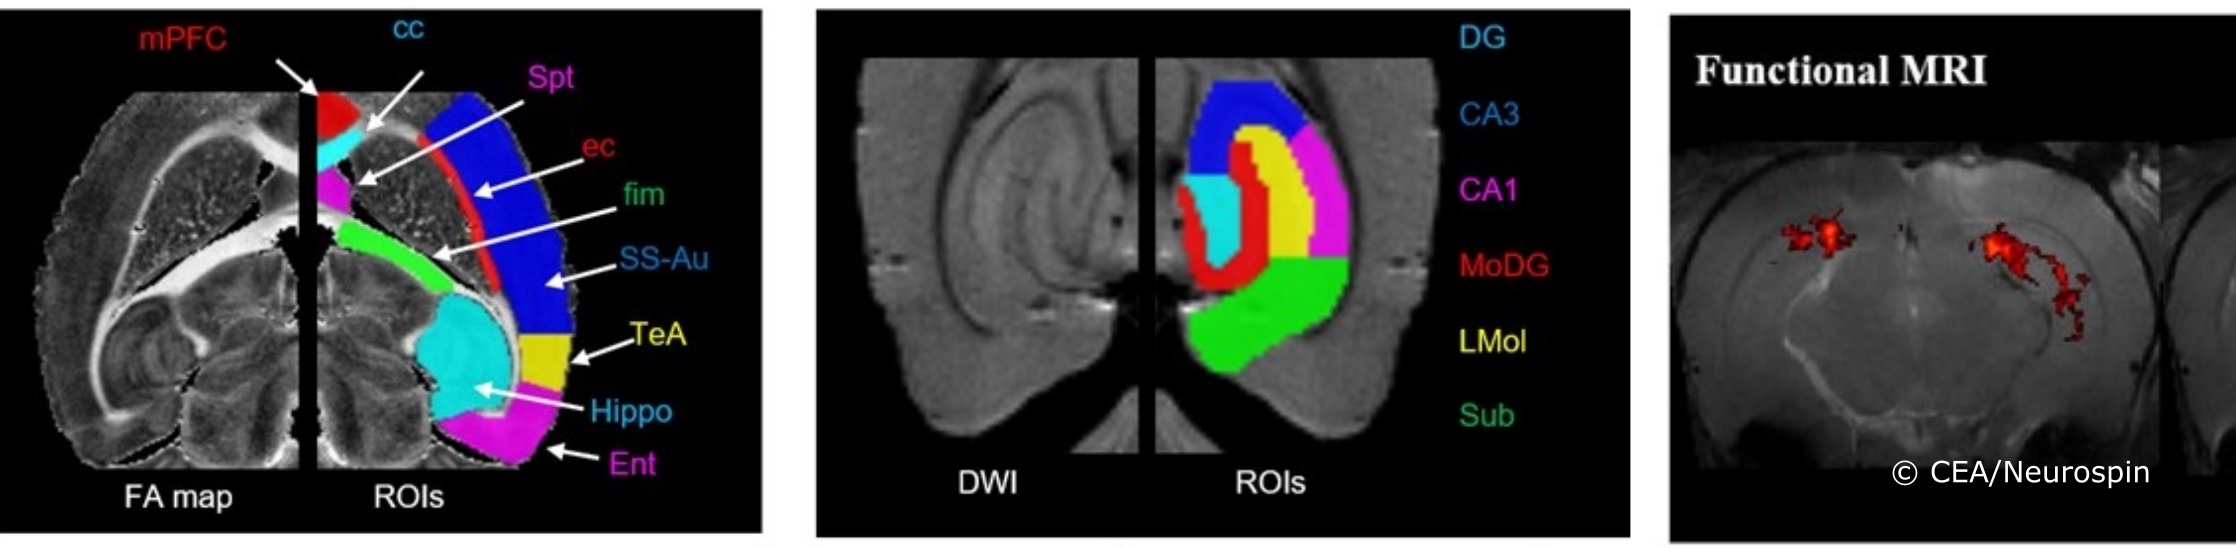

NeuroSpin dispose d’un imageur 17,2 Tesla de la société Bruker BioSpin. L'IRM 17,2 T est le système d’imagerie préclinique horizontal le plus puissant au monde. L’espace disponible à l’intérieur des gradients (85 mm) permet l’imagerie de petits animaux (souris, rats). En dehors d’un ultra-haut champ magnétique, une autre particularité de ce système est que son gradient de champ magnétique est capable de produire 1000 mT/m (approximativement 15 fois plus puissant que ce qu’il est possible de faire avec des scanners cliniques). Grâce à ce système, nous sommes capables d’acquérir des images avec une résolution isotrope de 25 µm. Nous disposons d’une variété d’antennes radiofréquences adaptées à des applications spécifiques : antennes de surface et antennes volumique pour les cerveaux de rats et de souris et des micro-antennes d’un diamètre allant de 700 µm à 2 mm pour les échantillons et enfin des antennes de surface à noyau-X (13C, 31P) pour la spectroscopie.